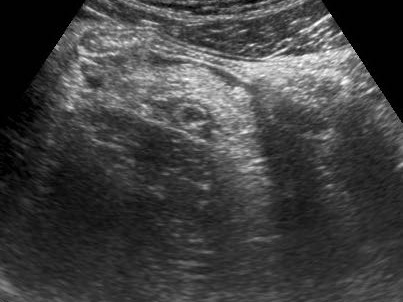

Cấu trúc phân lớp thành ruột thừa

Bờ giảm âm không đều, bất đối xứng và mất cấu trúc phân lớp thành ruột thừa là dấu hiệu gợi ý thủng hoặc thủng sắp xảy ra.

Ở giai đoạn này luôn có mô mỡ viêm phong phú (đầu mũi tên).

Cấu trúc phân lớp thành ruột thừa càng bị tổn thương nhiều, khả năng thủng càng cao.

Dấu hiệu đầu tiên là những thay đổi giảm âm trong lớp dưới niêm mạc tăng âm.

Việc dự đoán thủng dựa trên hình ảnh siêu âm không thực sự đáng tin cậy và có ít hệ quả điều trị tại thời điểm đó.

Dịch tự do

Một lượng nhỏ dịch trong phúc mạc giảm âm (*) có ít giá trị chẩn đoán và có thể gặp trong cả viêm ruột thừa cấp chưa thủng (trái) lẫn viêm ruột thừa thủng (mũi tên) (giữa), nhưng cũng có thể gặp ở bệnh nhân có ruột thừa bình thường (phải).

Lượng dịch lớn hơn, đặc biệt nếu khu trú và/hoặc đục, thường kèm theo liệt ruột khu trú hoặc toàn thể, là dấu hiệu nghi ngờ thủng.

Thông thường những bệnh nhân này có tình trạng nặng, đau nhiều và CRP tăng cao.

Ở người phụ nữ 56 tuổi này với CRP 180, siêu âm phát hiện dịch trong phúc mạc đục (*) và có thể thấy ruột thừa viêm với sỏi phân (mũi tên).

CT xác nhận hai sỏi phân ở hố chậu phải với hình ảnh khí bất thường, nghi ngờ viêm ruột thừa thủng.

Chọc hút dưới hướng dẫn siêu âm xác nhận dịch mủ.

Phẫu thuật cấp cứu phát hiện viêm ruột thừa thủng với nhiễm bẩn mủ bốn góc phần tư ổ bụng.